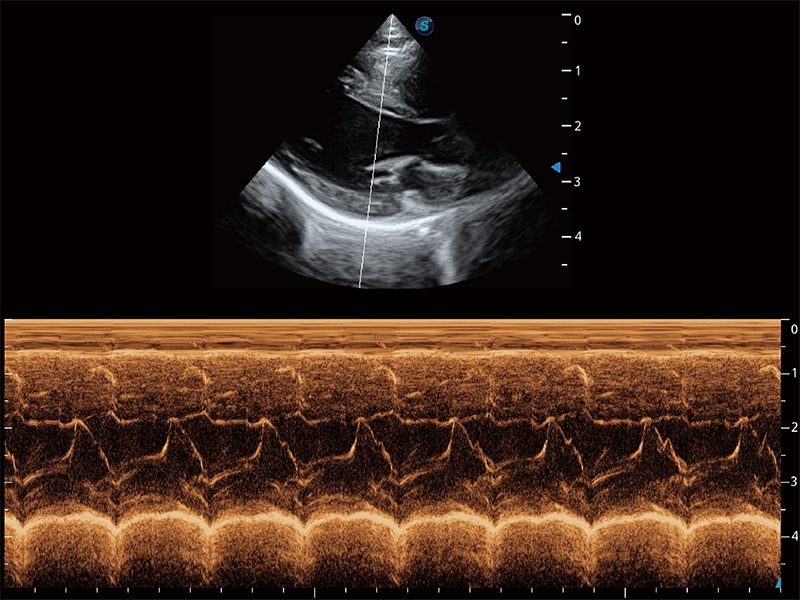

通过360度任意调节3条M型取样线,在同一心动周期上观察心脏不同位置的运动曲线,得到准确的心功能测量数据,有效评估心肌运动及左心室功能。

实时用颜色表示心肌组织运动,观察和定量组织的运动情況,对快速检测与评估心肌的灌注和活性、电传导及心肌收缩和舒张功能等均能提供重要的诊断信息。